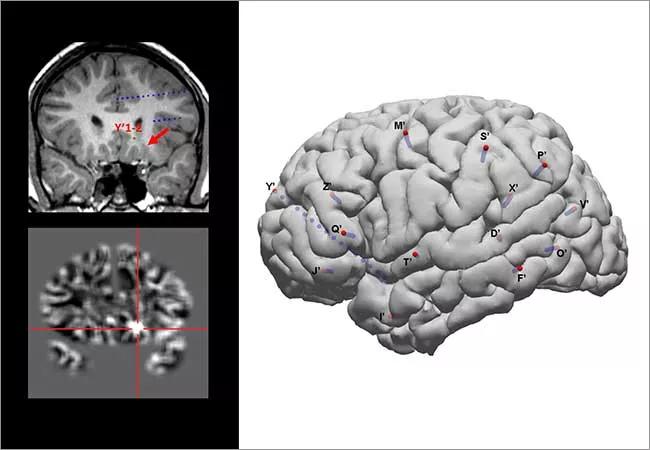

Figure 1. Presurgical evaluation results for the 11-year-old case patient in whom voxel-based morphometric MRI post-processing identified a subtle focal cortical dysplasia lesion. (A) Coronal T1-weighted MRI that served as the input to the MRI post-processing. (B) Gray-white junction image as the output of the MRI post-processing. The subtle abnormality is highlighted at the crosshairs, which corresponds to the arrow in panel A. (C) FDG-PET image showing hypometabolism involving the left orbitofrontal region. (D) Ictal SPECT localization showing hyperperfusion involving the left orbitofrontal region. (E) Map of SEEG implantation in the patient. Implanted electrodes are shown in blue, with entry points shown in red. A depth electrode (Y’) was implanted to specifically target the subtle lesion on the MRI. (F) Ictal finding on SEEG during one of the patient’s habitual seizures. The solid red circle indicates the ictal onset at the most mesial contacts of the Y’ electrode (Y’1-2). The dashed red circles indicate the early spread to the left insular (Q’1-4) and left middle frontal (M’7-12) regions. The spread to the left middle frontal region can explain the patient’s semiology of eye movement. Location of the ictal onset contacts Y’1-2 is also reflected in panels A, C and D, showing that the SEEG results were highly consistent with the structural lesion.

SEEG evaluation with 14 electrodes in the left hemisphere (Figure 1E) confirmed an epileptogenic zone in the left orbitofrontal region (orbital gyrus/olfactory sulcus) that coincided with the MRI abnormality, with an epileptic network including the left orbitofrontal region, left anterior insula/frontal operculum and left middle frontal gyrus that was responsible for her clinical seizures. Twenty-six seizures were captured, and they demonstrated her highly stereotyped semiology of eye movements. They were also highly consistent electrographically. Ictal onset was seen at the electrode contacts at the MRI lesion, and clinical onset occurred only after the seizure had spread to the middle frontal gyrus (where the frontal eye fields reside), explaining the semiology of eye movements (Figure 1F).